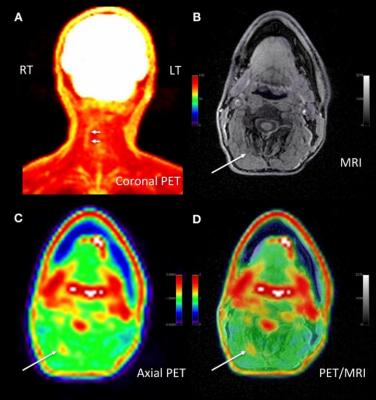

Adult male with decades of right neck pain, discomfort and tightening following birth injury. The patient had failed multiple standard therapeutic maneuvers before presenting for 18F-FDG PET/MR imaging. Images shows abnormally elevated FDG uptake (white arrows; SUVmax = 1.2) observed in a linear pattern in the space in the posterolateral right neck, between the oblique capitis inferior and the semispinalis capitis muscles, where the greater occipital nerve resides. By comparison, the same region on the contralateral, asymptomatic side of the neck has an SUVmax = 0.7. This result encouraged a surgeon to explore the area. The surgeon ultimately found a collection of small arteries wrapped around the nerve in this location. The small arteries underwent lysis by the surgeon and the patient reported tremendous relief of symptoms. (A) Coronal thick slab MIP of 18F-FDG PET. (B) Axial LAVA FLEX MRI through the cervical spine. (C) Axial PET at the same slice as the axial MRI. (D) Fused axial PET/MRI. Image courtesy of Cipriano, et al., Stanford University, CA.